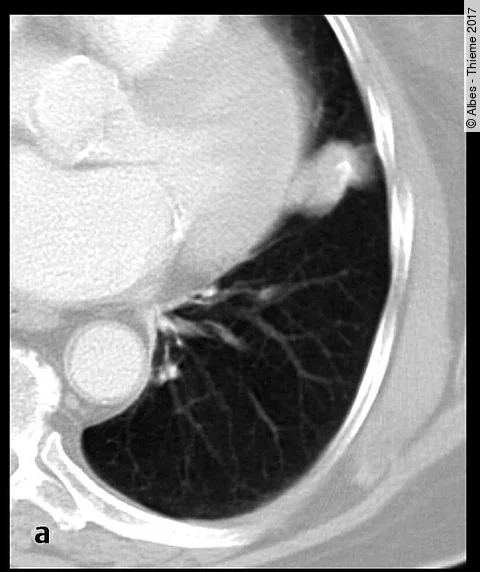

Wir haben gefragt: In dem größeren Lungenrundherd liegen Verkalkungen vor. Können diese als gutartiges Zeichen gewertet werden, so dass der Rundherd nicht weiter abgeklärt werden muss?